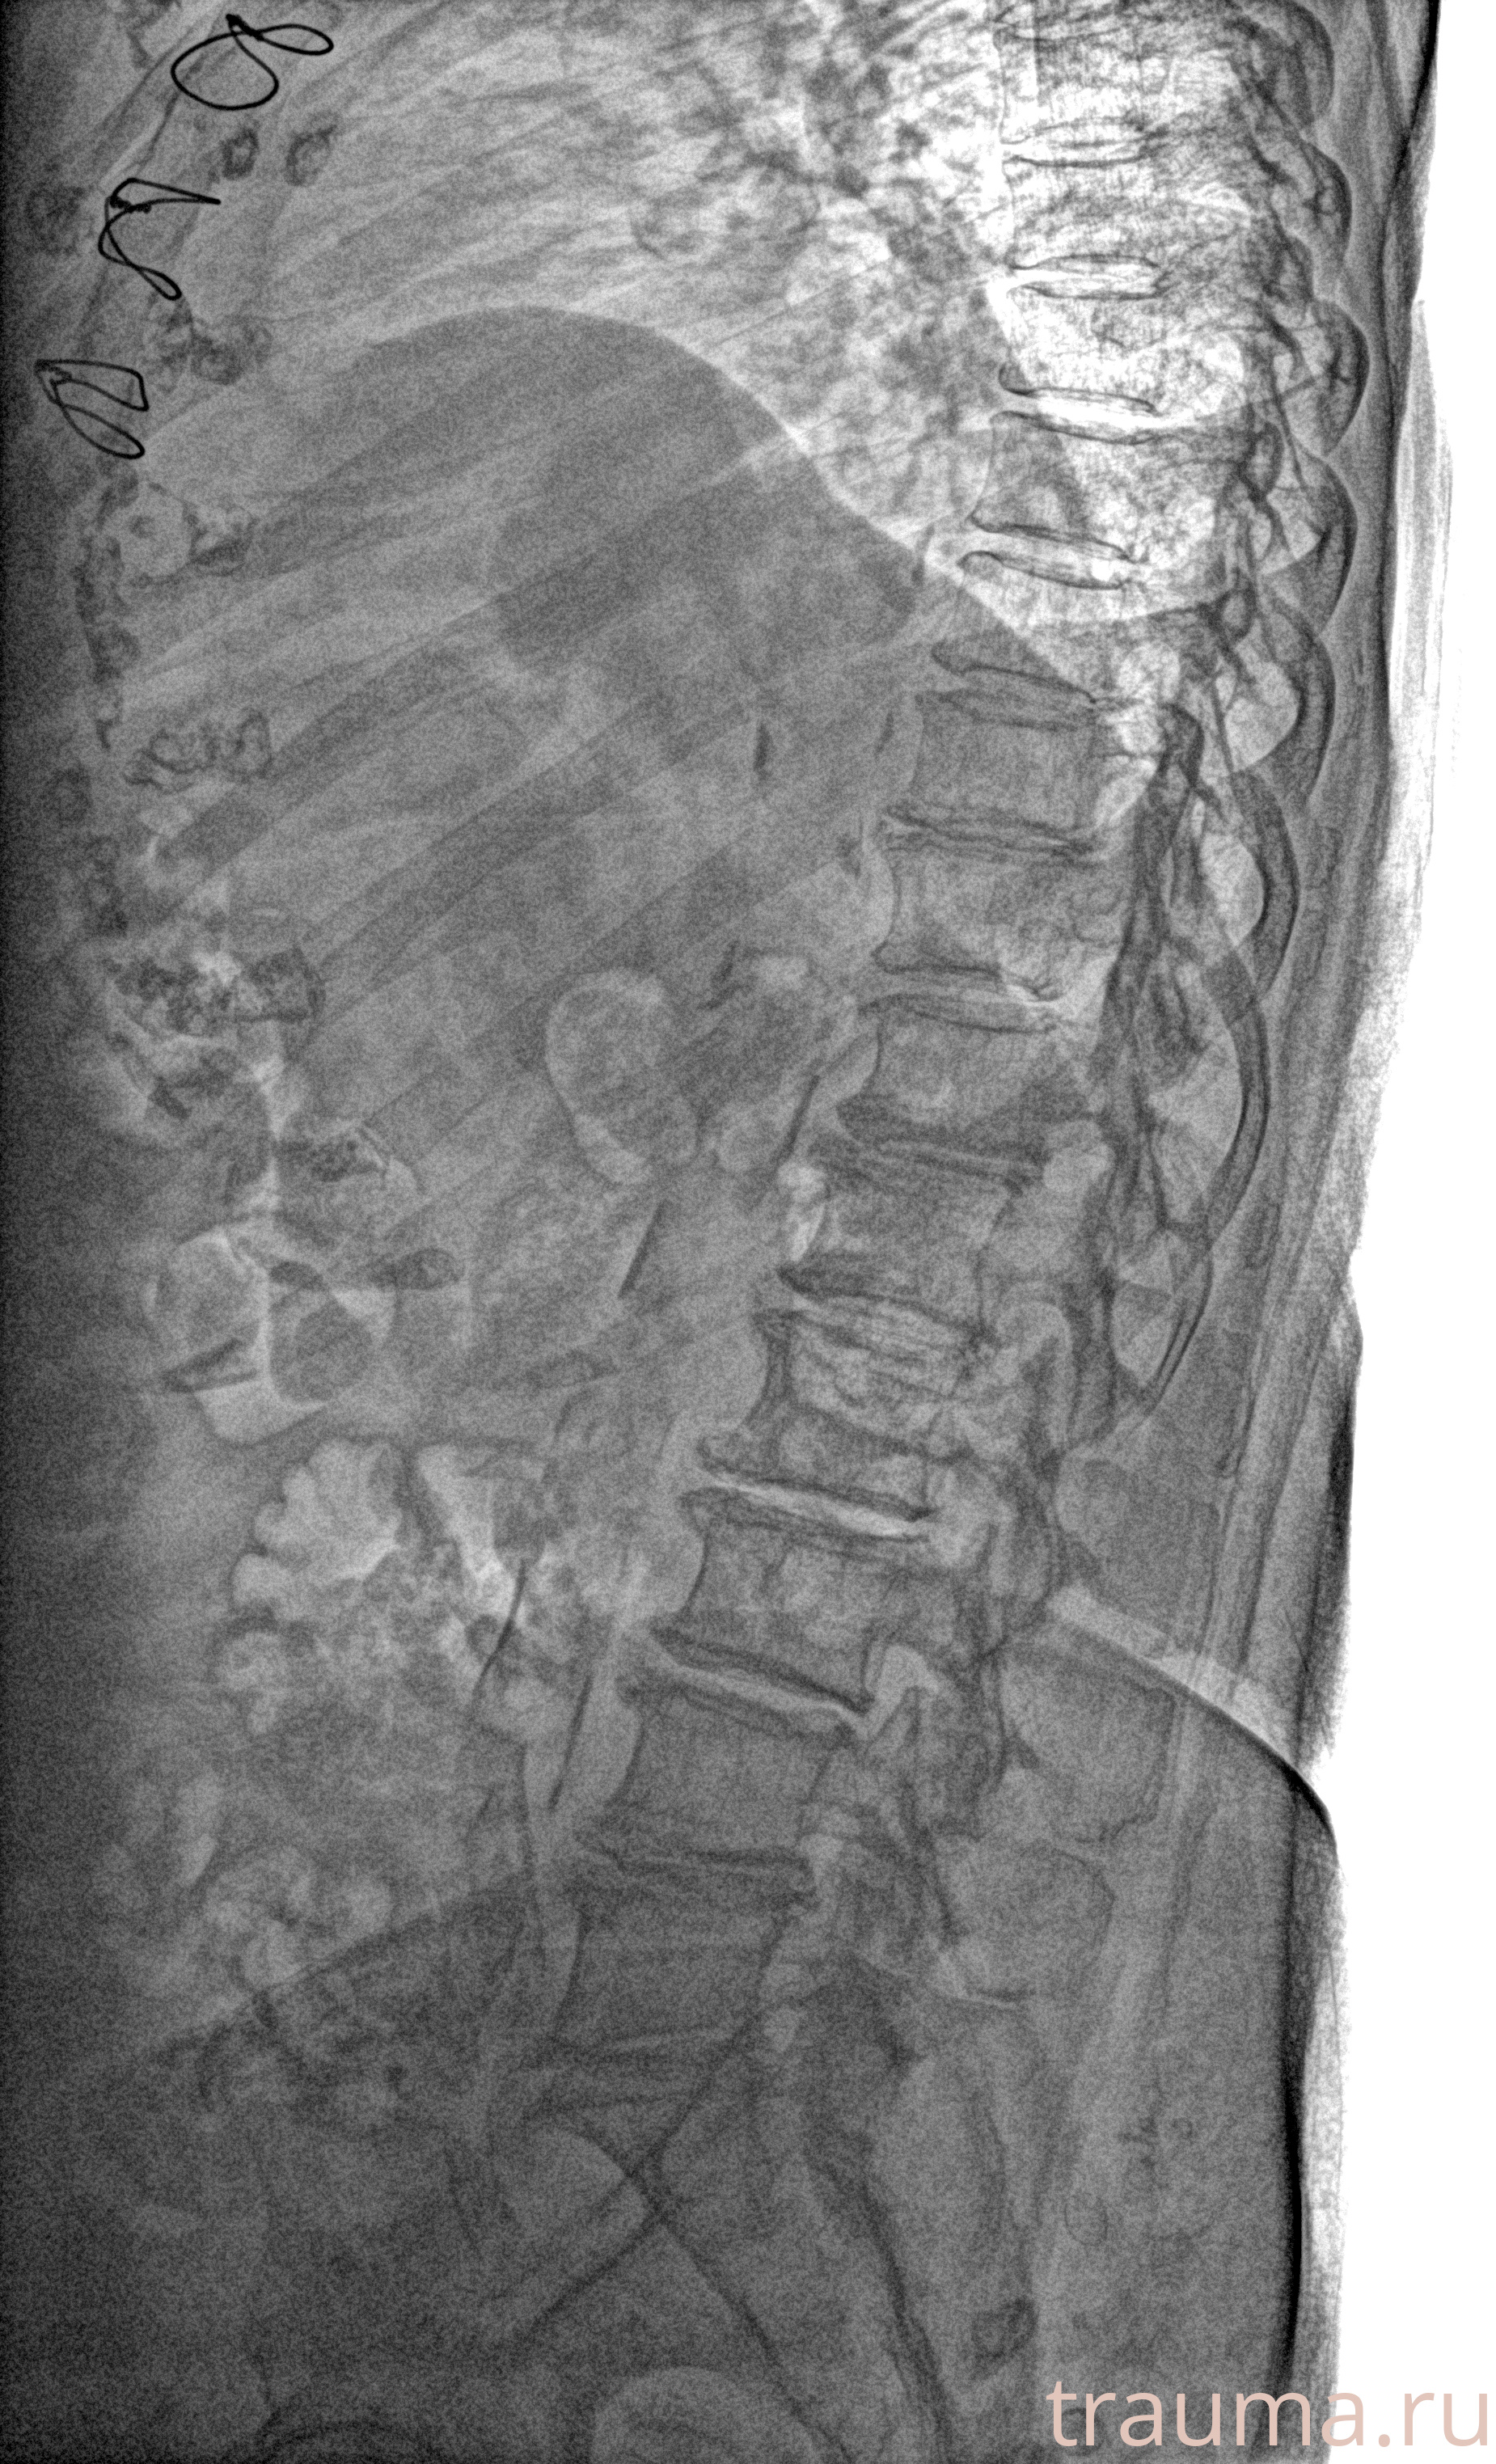

Рентгенограммы

Рентген на дому: по вашему адресу приезжает врач-рентгенолог, травматолог-ортопед с мобильным рентгеновским аппаратом, проводит диагностику травмы или заболевания, делает необходимые рентгенограммы, дает рекомендации по дальнейшему лечению. Получить качественные снимки в домашних условиях возможно благодаря уникальной методике, разработанной МосРентген Центром для института  Склифосовского